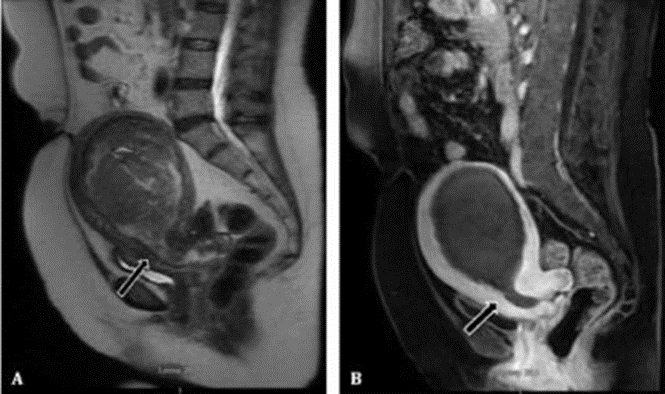

Pelvic MRI

A pelvic MRI scan specifically helps your doctor to see the bones, organs, blood vessels, and other tissues in your pelvic region—the area between your hips that holds your reproductive organs and numerous critical muscles. It can help find problems such as tumours in the ovaries, uterus, prostate, rectum, and anus. If you are pregnant, MRI may be used to safely monitor you or your baby. Excellent modality to diagnose endometriosis as MRI is sensitive to blood products.